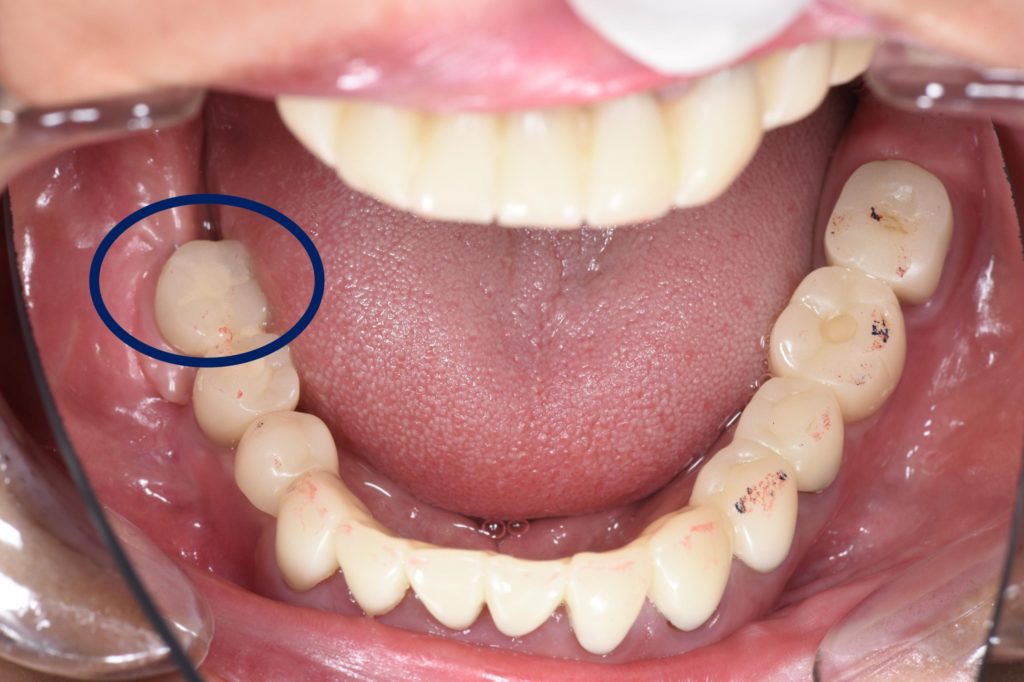

新幹線で通院して崩壊した状態からリカバリーした症例(抜歯即時インプラント、インビザライン、セラミック、フルマウス)

| 診断名 | 前歯審美障害(う蝕、歯牙の変色による)、全顎的咬合崩壊 |

| 年齢・性別 | 68歳 男性 |

| 治療期間・回数 | 40ヶ月 |

| 治療方法 | 全顎的な診査・診断のもと治療計画を立案した。臼歯部が失われていたため抜歯即時埋入インプラントと造成処置(硬・軟組織)を行ったあと、インプラント部の仮歯をアンカーとして矯正治療を行なった(インビザラインにて)。適切なアンテリアガイダンスがが得られた後に全顎的補綴処置を行なった。 |

| 費用 | 7,800,000円 |

| 注意点 | 全顎的に治療が必要なため治療期間がかかります。治療の中には保険治療が含まれていない項目があるため費用がかかります。治療期間中は仮の歯で生活する必要があり、仮歯の破損や脱離が起こることがあります。 |